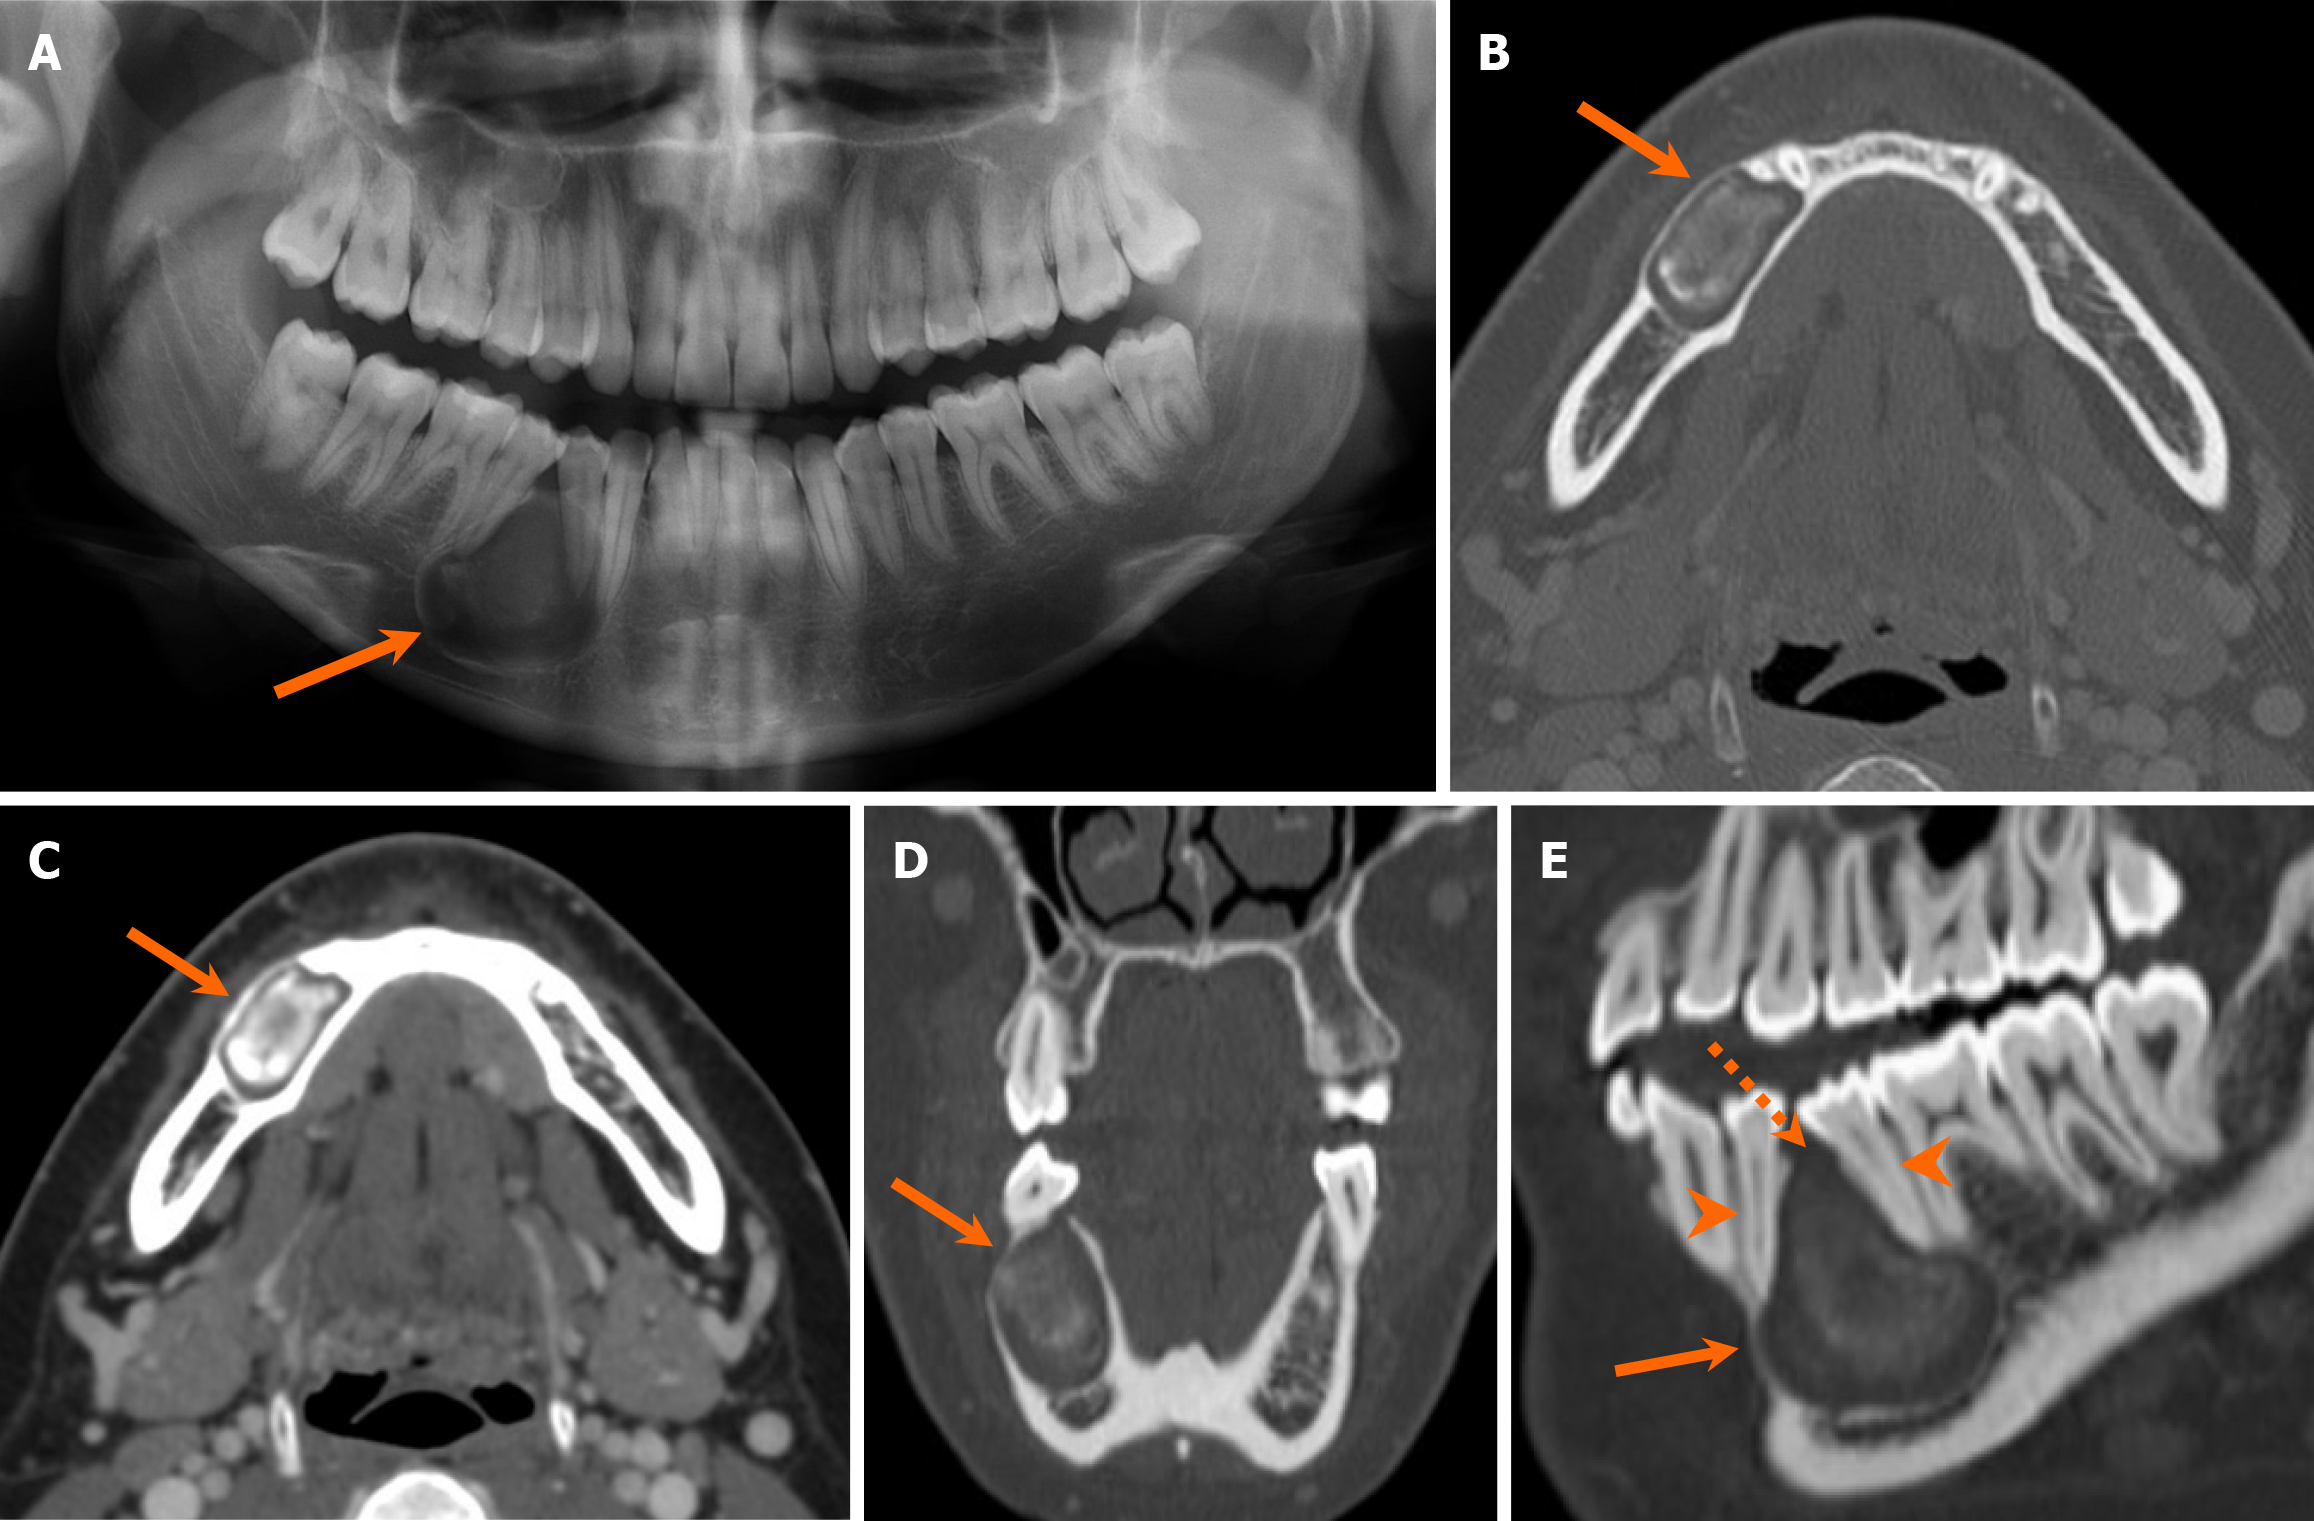

Discover the clinical significance of Schiller-Duval bodies, the pathognomonic histological hallmark of yolk sac tumors. Learn how these distinctive glomeruloid structures aid in the accurate diagnosis of endodermal sinus tumors. Explore the connection between these diagnostic markers, germ cell neoplasia, and elevated alpha-fetoprotein levels in this essential overview for pathology students and medical professionals.